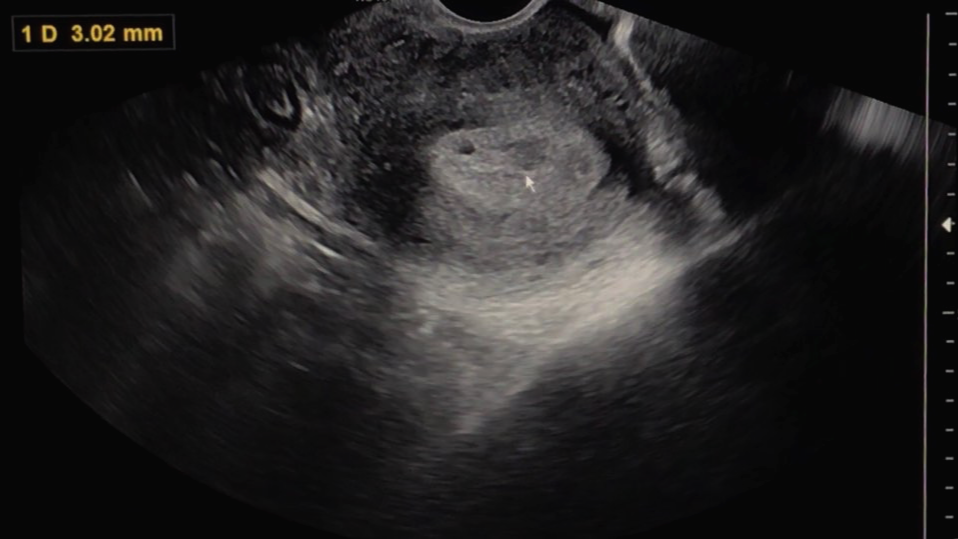

"아기집을 지은것 같긴한데. 그 집 안에 너 있는 거 맞는 거지?"

그리고 선생님은 초음파를 보면서 어떤 상태인지 한번 자세히 보자고 말씀하셨습니다.

아직은 확실하게 '아기집이 이거다!' 하고 보이지는 않는 상태이지만 와이프의 몸 안에 무언가가 생기기는 했나 봅니다.

확실히 아기집이 생겼다고 말씀을 안 해주시는 걸 보면 원장님 또한 아직은 조심스러운 상태이신 게 맞는 것 같습니다.

선생님은 문제가 없다면 10일 정도 후에는 아기집에서 아기의 심장이 뛰기 시작할 것이고, 14일 정도 후에 병원을 다시 한번 찾아오라고 하십니다. 그렇게 또다시 2주간 또 긴 기다림의 시간이 시작되는 것 같습니다.

아기를 보기 전에 아기가 지낼 아기집을 먼저 지었다는 사실이 놀랍습니다.